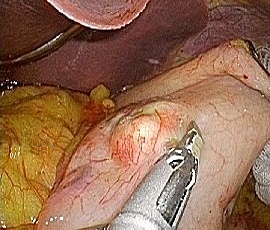

[胃GIST(消化管間質腫瘍)] 手術:腹腔鏡下胃局所切除術(ESD併施)

腹腔鏡画像